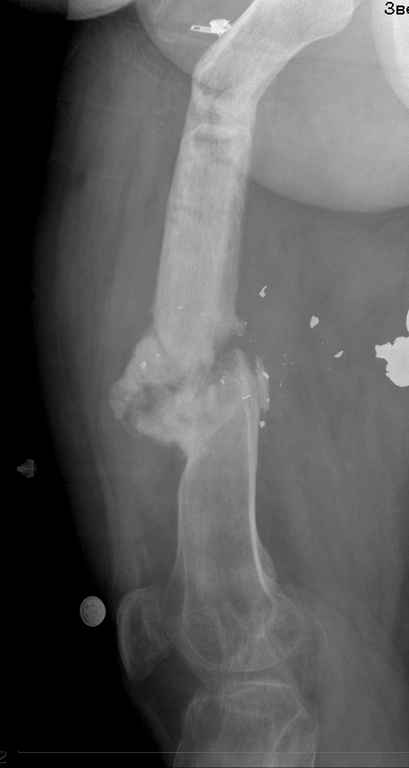

Re: ложный сустав бедра

посылаю снимки отдельно